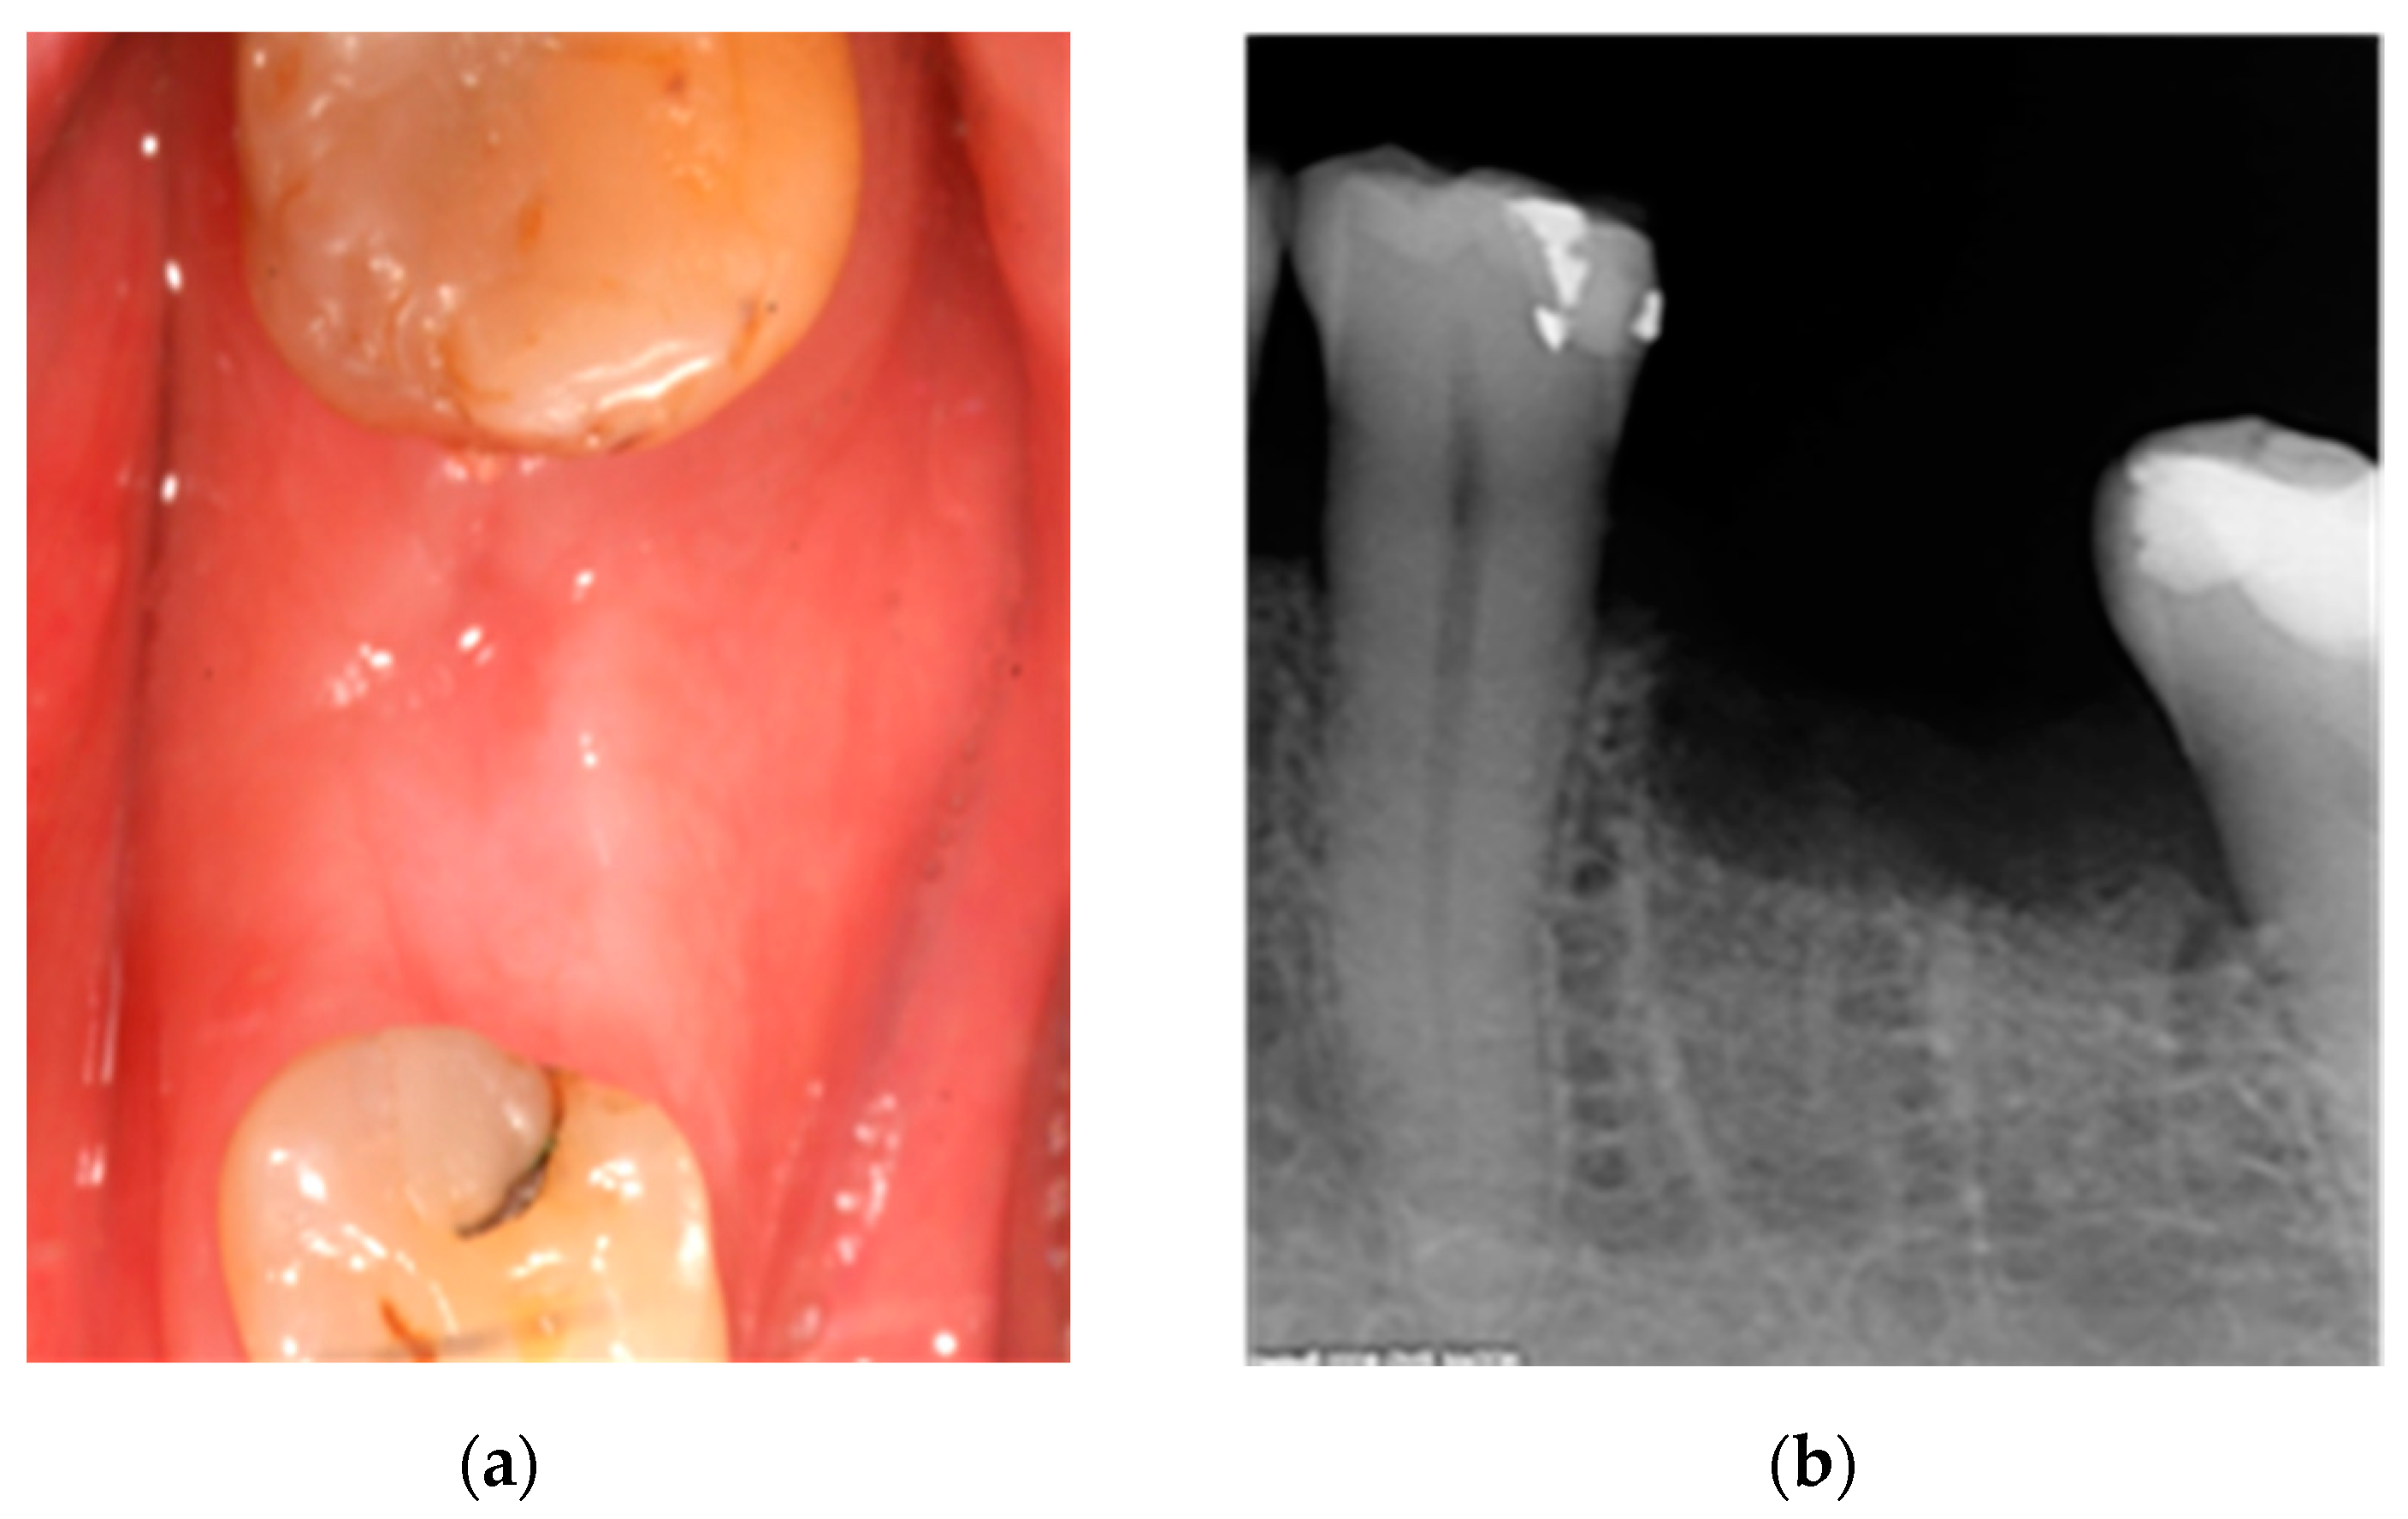

2.1. Case 1: Conservative Treatment

2.2. Case 2: Conservative Treatment Plus Surgery